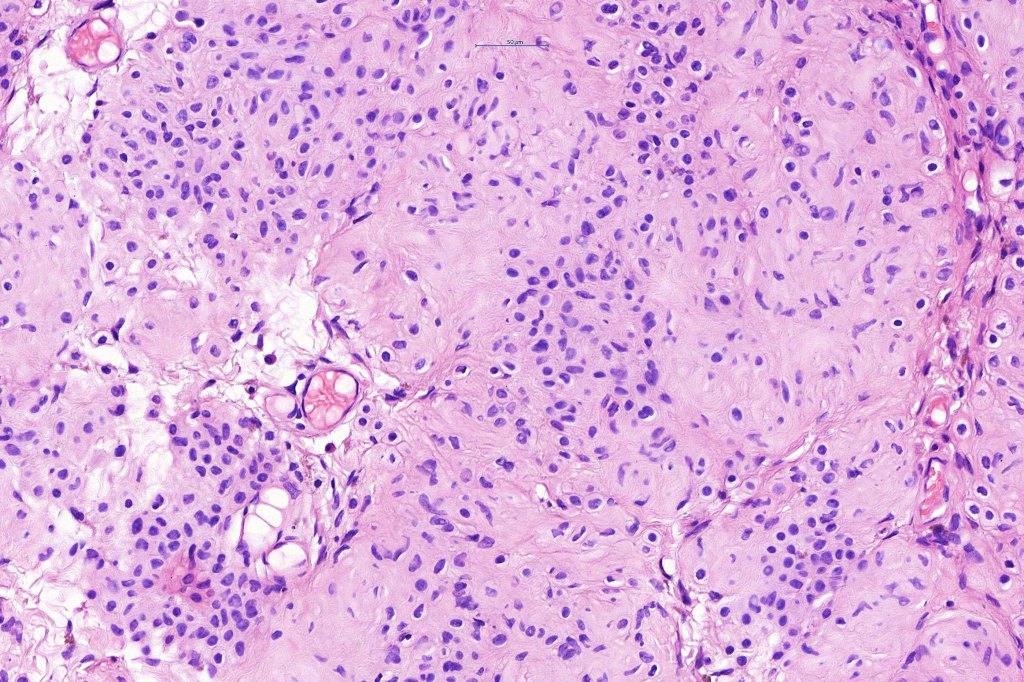

.Balloon cell change is most often seen in banal melanocytic nevi but it has also rarely been described in cellular blue nevus, dysplastic nevus, combined nevus, halo nevus & Spitz nevus. Lesions with <50% of balloon cells are sometimes described as nevi with balloon cells. Nevi with >50% balloon cells are described as balloon cell nevus.

.Balloon cell nevs genrally has uniform, hyperchromatic nuceli (as opposed to the vesicular nuclei with prominent nucleoli) seen in melanoma. Mitoses are absent.(In my experience, balloon cell melanoma is more common than balloon cell nevus).

. In some balloon cell nevi, the microvesicles may result in nuclear scalloping reminiscent of a sebaceous tumor. In cases where there is real doubt, immunohistochemistry (S100), SOX10) will resolve the problem.

The importance of the entity is that it must always be distinguished from balloon cell melanoma. All cases should be scrutinized very carefully for pleomorphism and mitotic activiy before rendering a diagnosis of balloon cell nevus.